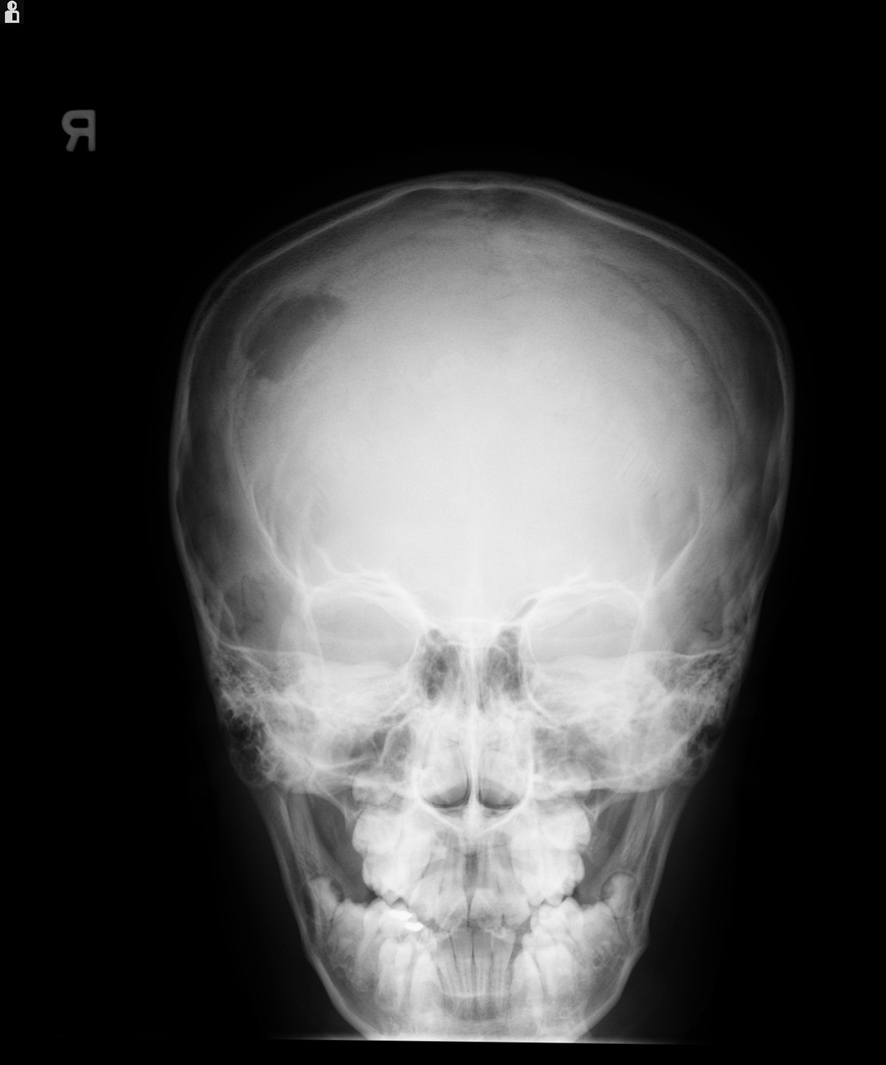

Laboratory results showed: hemoglobin - 12.4 g/dL, white blood cell count - 6,900/µL, and platelet count - 281,000/µL. Skull X-ray revealed a lytic lesion of the right parietal bone (Fig. 1). Computerized tomography (CT) scan of the head demonstrated 2.5 cm destructive lytic lesion at the right parietal bone with soft tissue mass measuring 2.5 х 1.5 cm, extending to the extra-axial intracranial space. Initial diagnosis was suspicious for Langerhans cell histiocytosis. Bone scan and chest CT scan did not reveal any distant metastasis. Patient had resection of the lesion which was reported as grade 1 SEF. Post-operative head CT scan and MRI showed residual lesion of 8 х 6 mm at the inferior and posterior aspect of the previously excised mass. Considering this rare tumor's poor response to chemotherapy and radiation, a decision was made to do a total resection. A right parietal craniotomy with gross total resection of the tumor, followed by cranioplasty was performed. Pathology report was consistent with SEF as before.

![]() Click for large image | Figure 1. X-ray of the skull showing lytic lesion in the right parietal region. |

Imaging and histopathology are the primary modes of diagnosis. Bone involvement presents as lytic lesions in X-ray. CT scan or MRI results depend on the site of the tumor. Typical histology of SEF consists of epithelioid cells arranged in strands, nests, and/or sheets, in a fibrotic and hyalinized stroma [5]. Mitotic figures are either scant or absent, and necrosis is uncommon. Although histomorphology of SEF suggests the tumor to be low grade, it could manifest signs of high-grade tumor clinically. SEF belongs to the family of fibrosing fibrosarcomas and appears to be the most malignant variant of this family of low-grade fibrosarcomas [6, 7]. The only immunostaining marker consistently reported positive, as in our patient, is Vimentin which is a general marker for soft tissue sarcomas and therefore not specific for SEF [3].